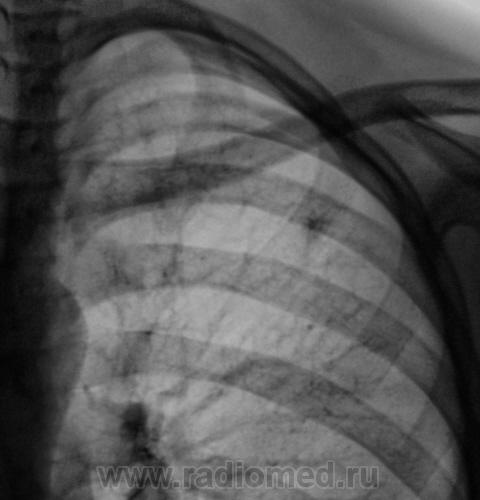

Первый срез.

Второй срез.

Конечно, ответственность, подросток и все такое... Но с другой стороны, кроме мелкого кальцинатика прицепиться больше не к чему. Все очаговоподобные тени видны при уменьшенной яркости и в местах пересечения сосуда с кортикалом ребра. Либо имеют "хвостик", что указывает на сосуд. Такое мое мнение.

Относительно кальцината без контроля это процесс не уточненой активности. У меня был случай когда ставили спонтанно излеченный очаговый плотные очаги которого в динамике полностью рассосались.